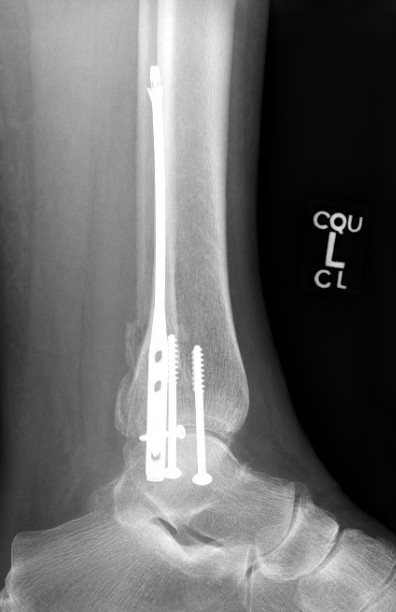

Hindfoot nail

Technique

Insertion point

- in line with 2nd metatarsal / center of heel pad

- junction of posterior 2/3 and anterior 1/3 heel

- should pass through anterior aspect posterior subtalar joint

Screw fixation

- distal screw fixation in calcaneum +/- talus with jig

- compression

- proximal screws medial to lateral